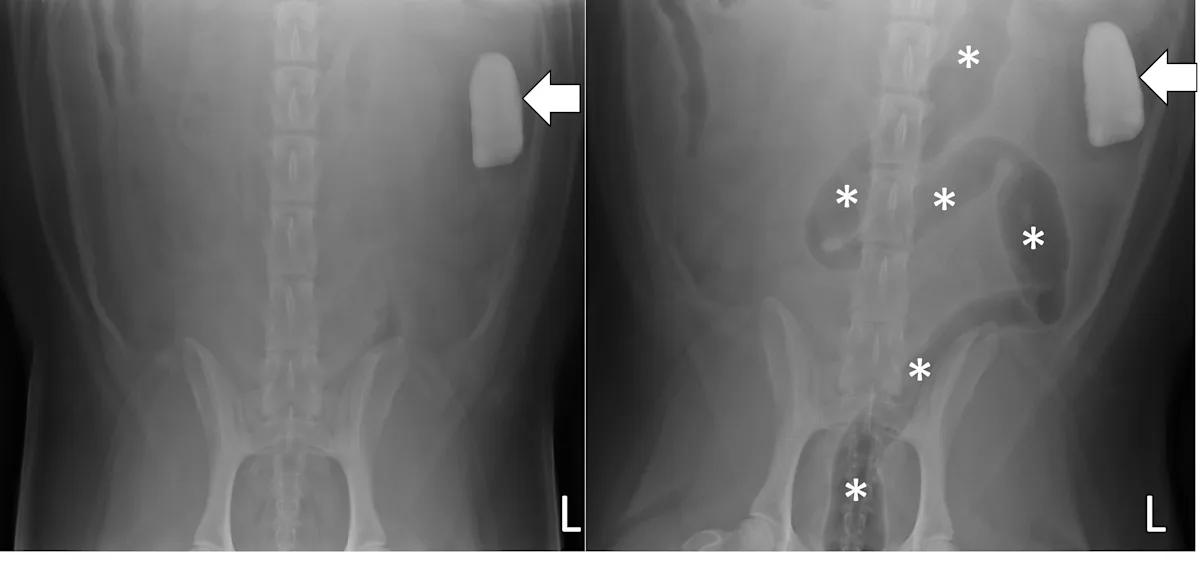

Pneumocolonogram

A pneumocolonogram can be performed to determine whether a foreign body is located in the colon or whether a focally dilated loop of intestine is part of the small bowel or colon (Figure 7).11 Sedation is often not necessary but can be used in uncooperative patients. Room air (3 mL/kg) should be administered into the rectum with an appropriately sized and lubricated red rubber catheter and syringe. Right lateral and ventrodorsal projections should be obtained immediately. The goal is to mildly dilate the entirety of the colon to the cecum with gas without overfilling the small intestine. The dose of air may need to be repeated to effect in some patients if there is inadequate filling of the entire colon.

Ventrodorsal radiographs of a 3-year-old spayed golden retriever with a small intestinal obstruction secondary to rock ingestion. Survey radiographs revealed the rock was in the left lateral abdomen but could not help determine whether the rock was in the small bowel or the descending colon (left, arrow). Pneumocolonogram was performed to mildly dilate the colon with gas (asterisks), confirming the rock was in the small bowel (right, arrow).